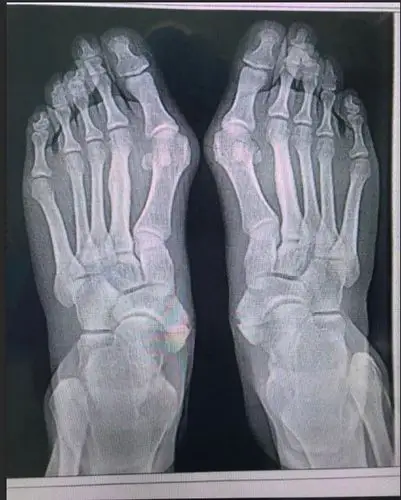

俗称"大脚骨",现行右足矫形,软组织,籽骨松解复位 chevron截骨 关节囊